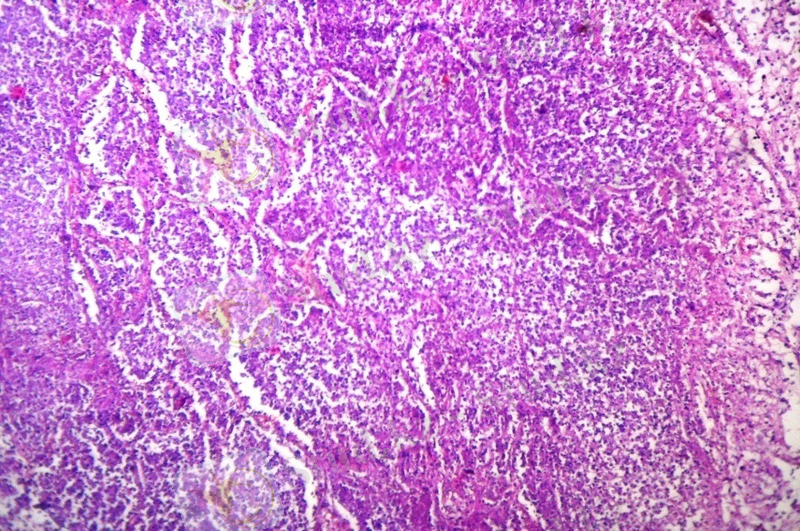

Микроскопиялық зерттеулерде каверналар әдеттегідей үш қабаттан тұрды. Фиброзды қабат жіңішке болды, грануляциялық қабаты нашар жетілген, аз мөлшерде лимфоидты элементтерден, нейтрофильдерден, макрофагтардан тұрады, бірлі-жарым эпителиоидты және Пирогов-Лангханс жасушалары кездесті. Казеозды некроз қабаты өте көлемді болды. Кавернаның айналасындағы өкпе паренхимасында көптеген себінді ошақтар анықталды, олардың ортаңғы бөліктерінде казеозды некроз, айналасында сирек орналасқан эпителиоидты және Пирогов-Лангханс типті көп ядролы алып жасушалар анықталады. Перикавитарлы аймақтарда сегментарлы және полисегментарлы серозды пневмония ошақтары анықталып, серозды экссудаттың казеозды некрозға ұшырауы нәтижесінде сегментарлы казеозды пневмония дамыған (1 сурет) . Казеозды ошақтардың ортаңғы бөлімдерінде ыдырау үрдістері дамып, жаңадан пневмониогенді қуыстар пайда болды. Казеозды массаларда көп мөлшерде ТМ анықталды (2 сурет) . Үлкен бронхтарда гранулематозды мезобронхиттер дамыды, ал субсегментарлы және кіші бронхтарда казеозды бронхиттер анықталды, олардың қабырғаларының сегментарлы және тоталды еруі байқалды (3 сурет) .

1-ші сурет. Казеозды пневмония ошағы. 2-ші сурет. Өкпе тінідегі ТМ жинақталуы

Гематоксилин және эозин бояуы. Ziehl-Neelsen бояуы.

Үлкейту х 200. Үлкейту х 400.